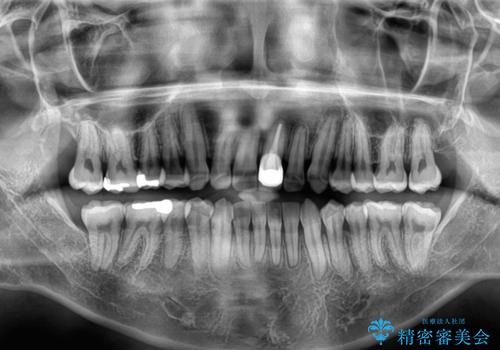

- 前歯のデコボコや八重歯を気にして来院された患者様です。

他院でワイヤー矯正を行うつもりでいらっしゃったそうですが、通院が難しくなったとのことで当院での治療を希望されて来院されました。

上下ともに歯列幅が狭く、その影響でデコボコになっていたため、ワイヤー装置を用いて歯列を側方に拡大しながら、デコボコを解消していくこととしました。